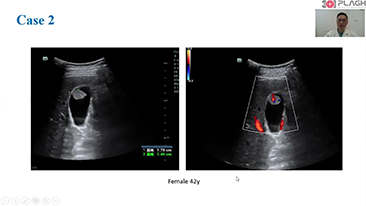

ImĂĄgenes generales

Las soluciones de imĂĄgenes generales de Resona de Mindray ayudan al personal clĂnico a realizar diagnĂłsticos y obtener resultados de tratamiento mĂĄs precisos y eficientes a travĂ©s de sondas para aplicaciones de subdivisiĂłn integrales y herramientas de aplicaciĂłn clĂnica eficientes.